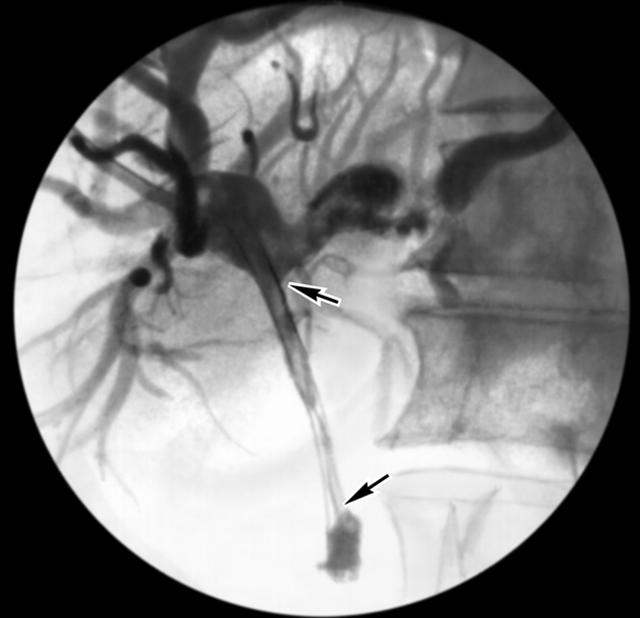

Рис. 2б). Холангиограммы больного со стриктурой общего желчного протока: после дилатации общего желчного протока в него введен пластмассовый эндопротез (указан стрелками).